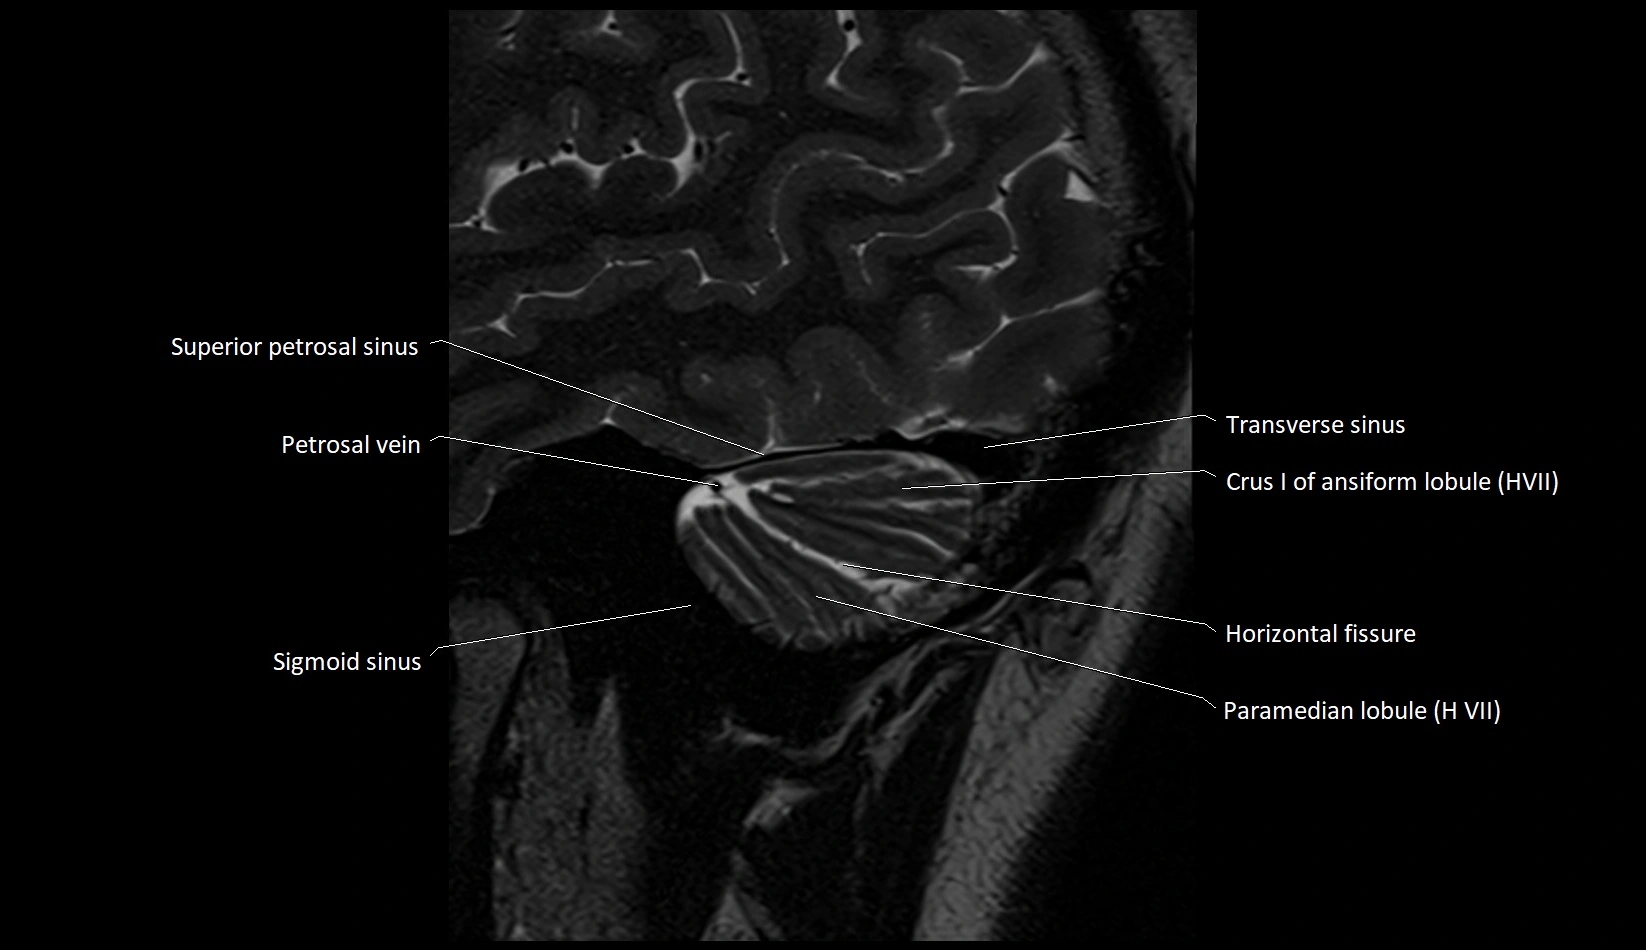

MRI images